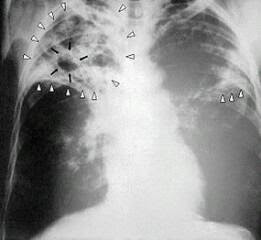

Tuberkulosis (selanjutnya disingkat TBC atau TB) adalah penyakit menular yang disebabkan kuman mycobacterium tuberculosis. Ketika seseorang yang menderita TB batuk, bersin, bicara atau meludah, mereka memercikkan kuman TB ke udara dan terhirup oleh orang lain. Seseorang yang tertular kuman TB belum tentu menjadi sakit. Kuman TB dapat menjadi tidak aktif (dormant) selama bertahun-tahun dengan membentuk dinding sel berupa lapisan lilin yang tebal. Bila sistem kekebalan orang tersebut menurun, kemungkinan menjadi sakit TB menjadi lebih besar. (Hasil sinar-x seorang penderita TB, panah putih menunjukkan adanya infeksi. Panah hitam menunjukkan adanya lubang. Ilustrasi dari sini ) TBC adalah penyebab kematian nomor dua dari golongan penyakit infeksi (setelah HIV/AIDS). Walaupun angka kematian akibat TB telah menurun sebesar 2% per tahun, masih rendah dibanding negara tetangga seperti Kamboja yang penurunan kasus TB-nya sebesar 4 atau 5 % per tahun. Artinya, pemerintah banyak memili...